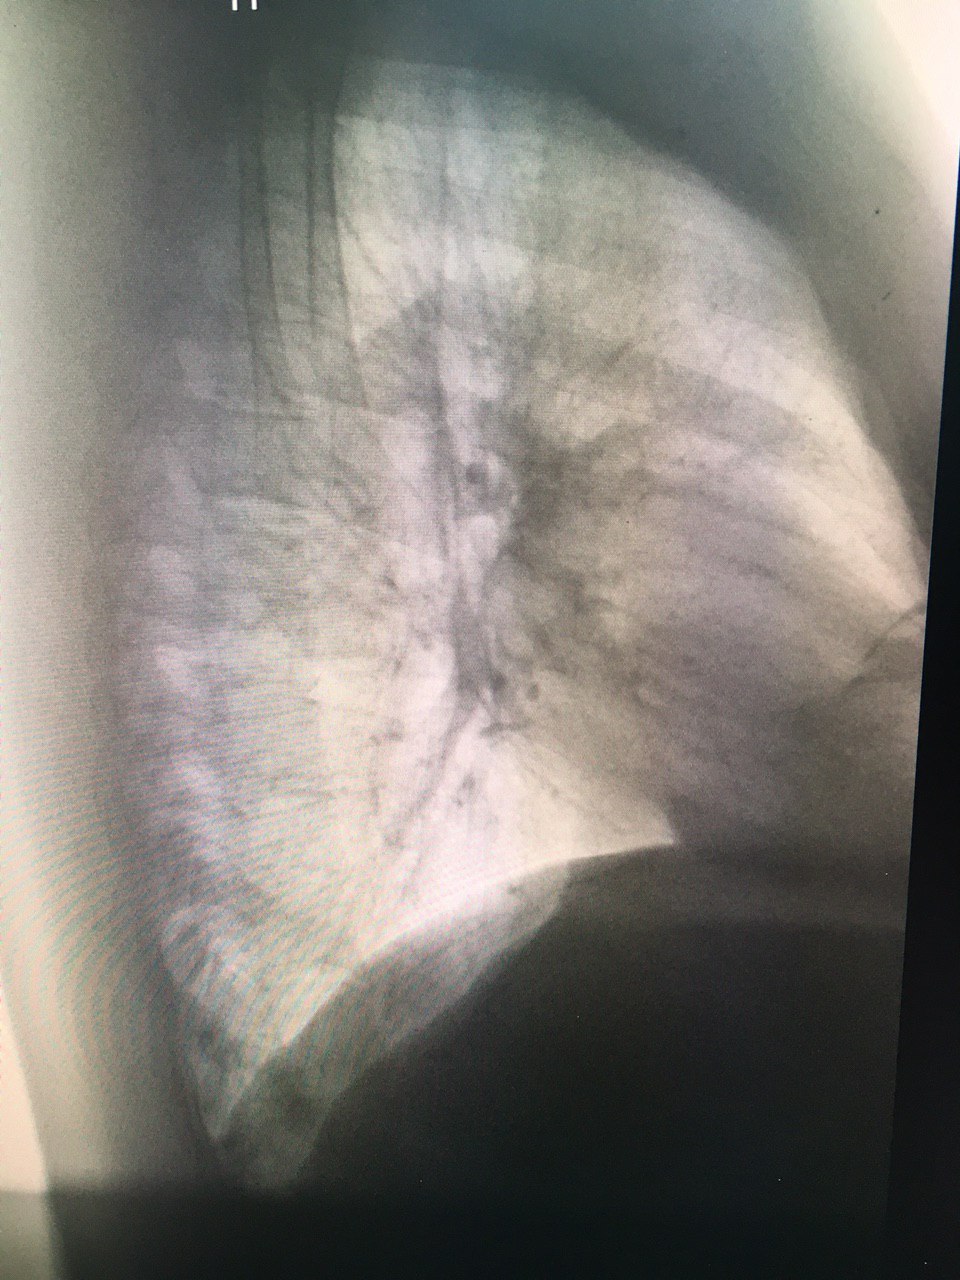

Позитив ?

Ладно. Хотел в позитиве бок глянуть

Позитив)

Что-то есть ☺️😏

Конечно диск бы увидеть

Унёс((( почему то кажется, что все таки сосок. Справа симметрично прохожая тень

Возможно вы правы)